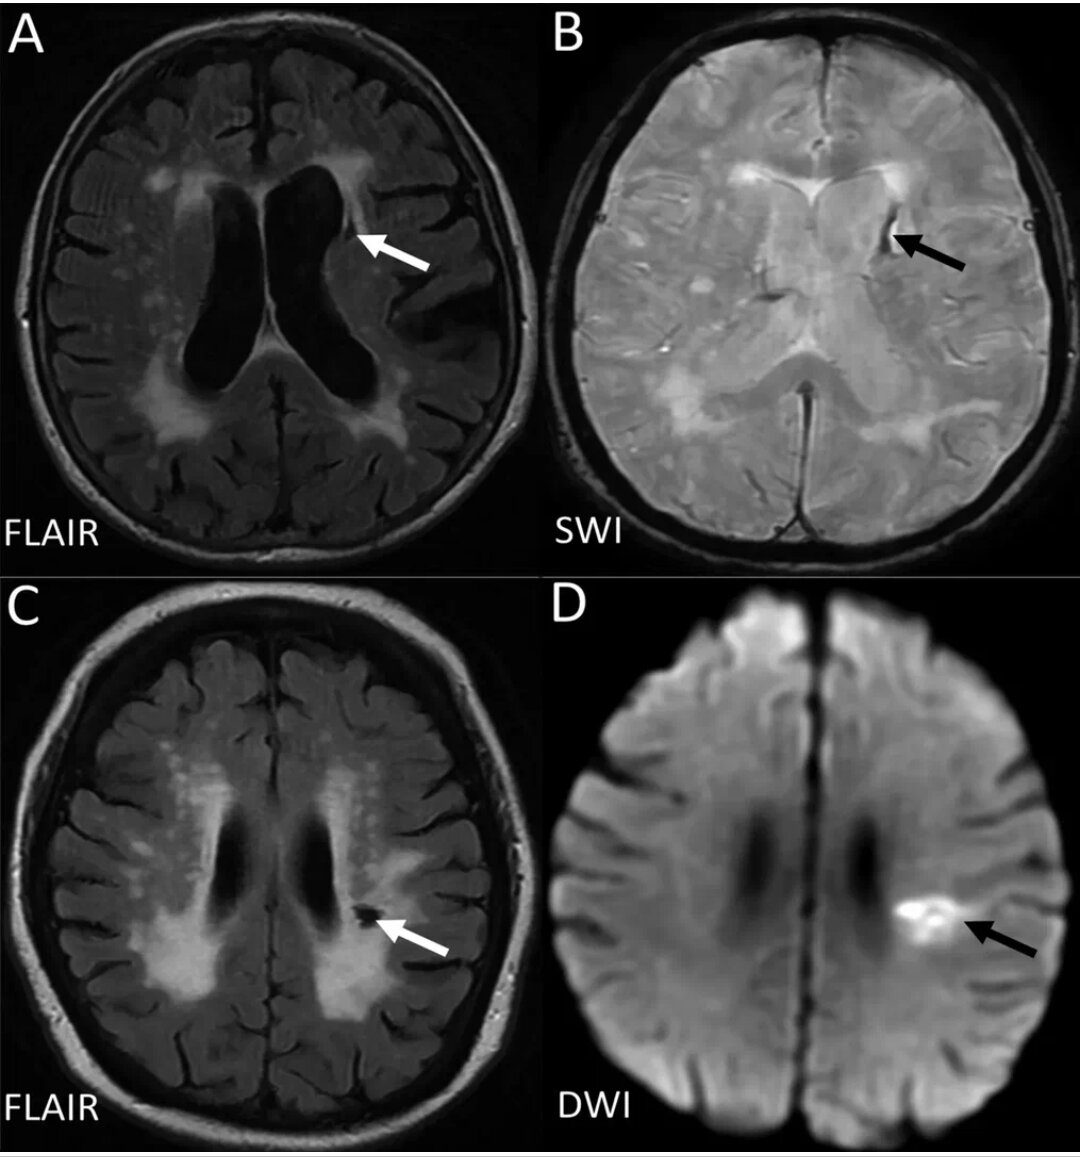

Fazekas grades. Инсульт на Dwi. Лейкоареоз Фазекас. Инсульт Dwi Flair несоответствие. Brain stroke MRI.

Fazekas grades. Инсульт на Dwi. Лейкоареоз Фазекас. Инсульт Dwi Flair несоответствие. Brain stroke MRI.